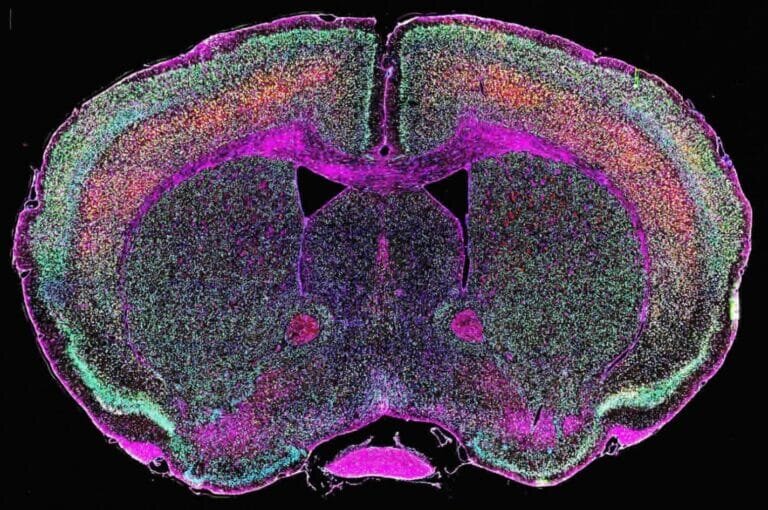

Визуализация экспрессии эндогенных ретровирусов в мозге / © Nath lab, NINDS, NIH.